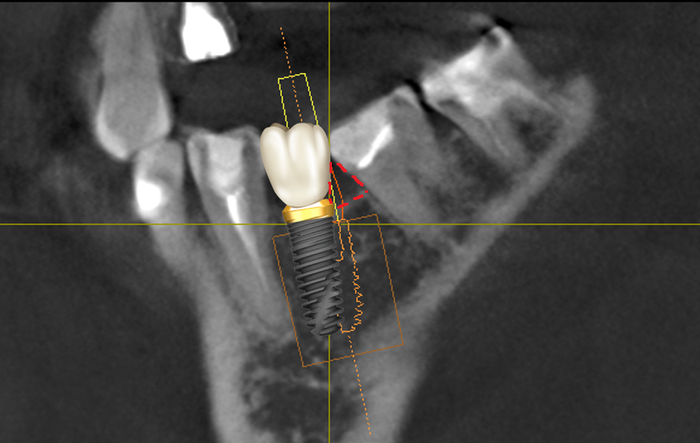

Хирург тупо смещает имплантат, а ортопед сдаёт вот такую ущербную коронку на основной жевательный зуб:

Чем плох такой вариант? Да тем, что между коронкой на имплантате и коронковой частью семерки образуется так называемый «черный треугольник»:

Там постоянно будут скапливаться остатки пищи и зубной налет. Это приведёт к воспалению и убыли костной ткани как в области установленного имплантата, так и седьмого зуба. Всё это закончится удалением имплантата и зуба. Следовательно, необходимо стремиться к чему-то такому: